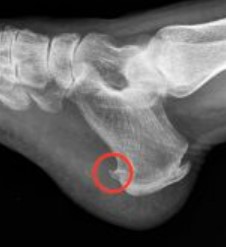

Qué es el espolón calcáneo: Principales causas y sus tratamientos

¿En alguna ocasión has sentido un fuerte dolor en el talón al apoyarlo en el suelo? Probablemente te has preguntado...